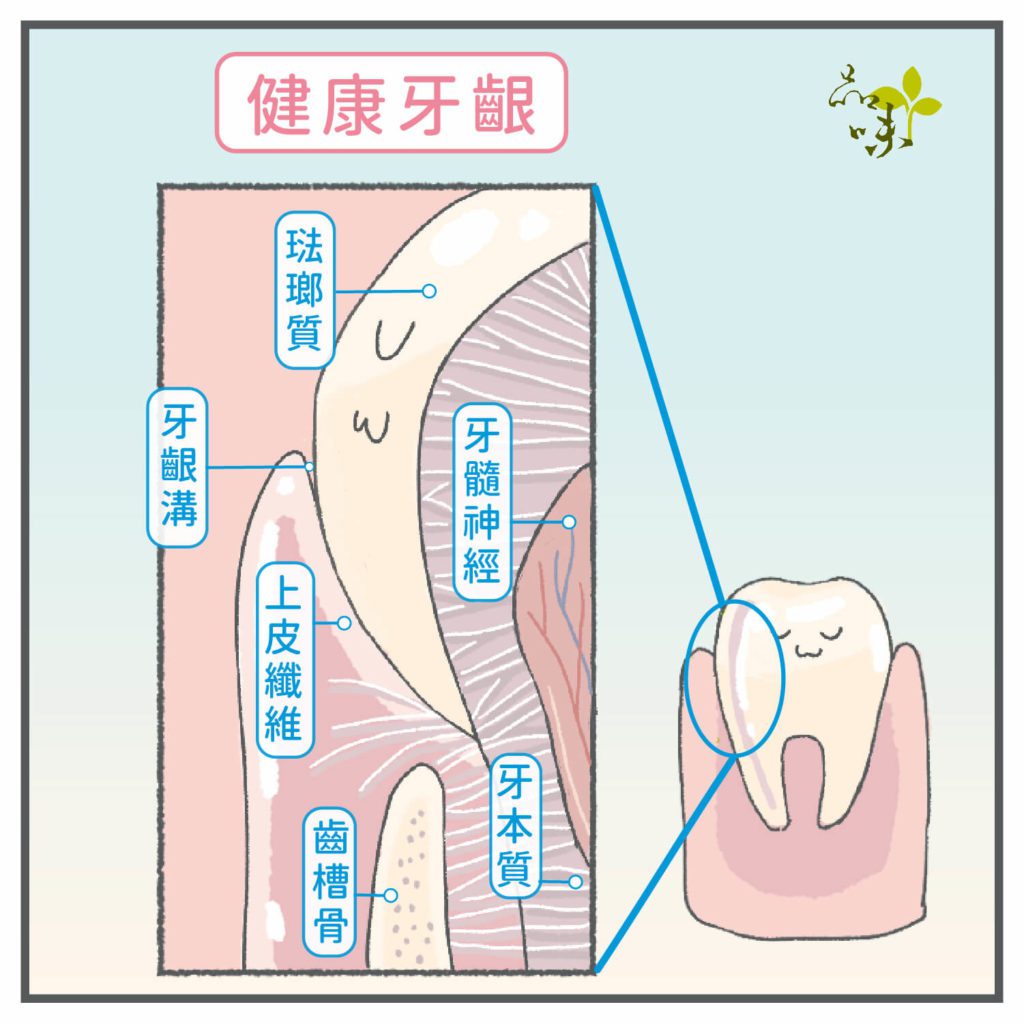

牙齒剛生長出來時,牙根是被牙肉緊緊包圍的,只有上部的牙冠會露出牙肉表面。

某天,牙肉開始「倒退」、「減少」,讓牙根逐漸裸露出來,照鏡子一看感覺牙齒變長了──可能就是我們常講的「牙齦萎縮」現象。